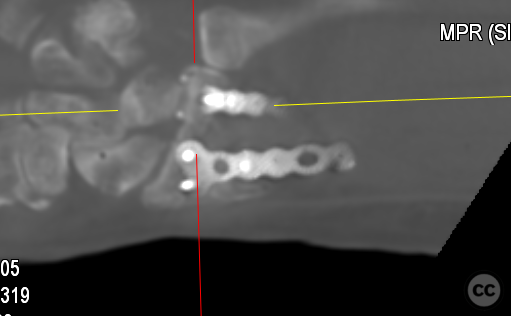

Anatomical surgical approach:  A longitudinal incision was made over the flexor carpi radialis (FCR), zigzagging over the wrist crease. Subcutaneous dissection and incision of the FCR tendon sheath were performed, followed by transection of musculus pronator quadratus fibers along the radial border of the distal FCR. The FCR tendon was retracted ulnarly, and the antebrachial fascia incised. Musculus flexor pollicis longus was identified and retracted ulnarly. The pronator quadratus was incised along its radial border and the watershed line, then elevated subperiosteally to expose the distal radius. Extended distal release of the FCR allowed wide exposure of the ulnar aspect of the lunate facet and volar lip. The flipped volar ulnar fragment was de-rotated and provisionally fixed with a Kirschner wire. Ligamentotaxis for radial styloid reduction was achieved using Kirschner wires in the scaphoid and distal radius, with a wire spreader applied for distraction. Provisional fixation was achieved with multiple Kirschner wires. A mini-fragment T-plate, cut and shaped as a hook plate, was applied to the volar ulnar lip fragment, fixed with bicortical screws, and used to engage dorsal fragments. The radial styloid was addressed with a contoured T-plate, similarly fixed with bicortical locking screws. Final multiplanar fluoroscopy confirmed anatomical reduction and hardware placement.

The flipped volar ulnar articular margin fragment was irreducible by closed means due to capsular attachment and required direct open de-rotation and fixation. The impaction and proximal displacement of the radial styloid fragments were challenging due to persistent traction from musculus brachioradialis and scaphoid pressure; ligamentotaxis using Kirschner wire spreader over the scaphoid facilitated reduction. Fragment-specific fixation was necessary: a custom-shaped hook plate for the volar ulnar lip fragment provided stable fixation and prevented dorsal instability, while a separate T-plate addressed the radial styloid. Bicortical locking screws were used to secure both plates, with some screws engaging dorsal fragments from the volar side. Careful adaptation of pronator quadratus over hardware minimized risk of musculus flexor pollicis longus irritation. Additional suture stabilization of radiocarpal ligaments to pronator quadratus provided secondary ligamnetal support.

Orthopaedic implants used:   - 1.0 mm Kirschner wire (provisional fixation) - 1.8 mm Kirschner wire (scaphoid traction) - 2.0 mm Stryker mini fragment T-plate (cut/shaped as hook plate) - 2.4 mm T-plate (radial styloid fixation)